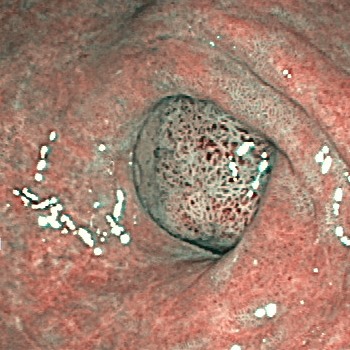

| ˆف’×ل‡(ƒsƒچƒٹ‹غٹ´گُ‚ة‚و‚é‚à‚ج) | |

| ˆف’×ل‡پAڈ\“ٌژw’°’×ل‡‚جŒ´ˆِ‚ج‘½‚‚ح ƒwƒٹƒRƒoƒNƒ^پ[ƒsƒچƒٹ‹غٹ´گُ‚ة‚و‚é‚à‚ج‚إ‚·پB ‚ـ‚½پAƒsƒچƒٹ‹غ‚جژ‘±ٹ´گُ‚حˆفٹà‚جŒ´ˆِ‚ة‚à‚ب‚è‚ـ‚·پB “–‰@‚إ‚حگد‹ة“I‚بڈœ‹غژ،—أ‚ً‚¨‚·‚·‚ك‚µ‚ؤ‚¢‚ـ‚·پB ƒsƒچƒٹ‹غ‚ج‰ًگà‚ح‚±‚؟‚ç •گ“c–ٍ•iچH‹ئ‡ٹ‚جHP‚ض‚جƒٹƒ“ƒN پ¦ƒsƒچƒٹ‹غ‚جژتگ^‚ح•گ“c–ٍ•iچH‹ئ‡ٹ‚©‚ç’¸‚«‚ـ‚µ‚½پB |

| ڈ\“ٌژw’°’×ل‡ | ڈ\“ٌژw’°SMT |

| ڈ\“ٌژw’°ٹàپi‚ك‚¸‚炵‚¢ڈا—ل‚إ‚·پj | “¯ڈا—ل‚جNBI‰و‘œپiژîل‡ŒŒٹا‹’²ژB‰eپj |